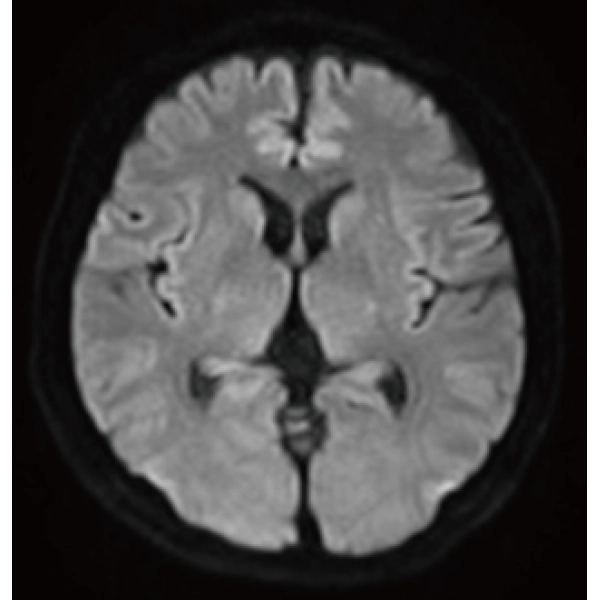

Deep Learning technology*8 enables image quality adjustment after imaging is complete. It optimize SNR and improve image sharpness by processing MRI signals in stages (k-space signal processing). This brings super-resolution and reduces truncation artifacts.

"DLR" is applicable to all body parts and promotes high speed imaging and diagnostic efficiency

IP-RAPID x DLR Plus can also shorten imaging time, allowing more images to be taken in the same examination time.